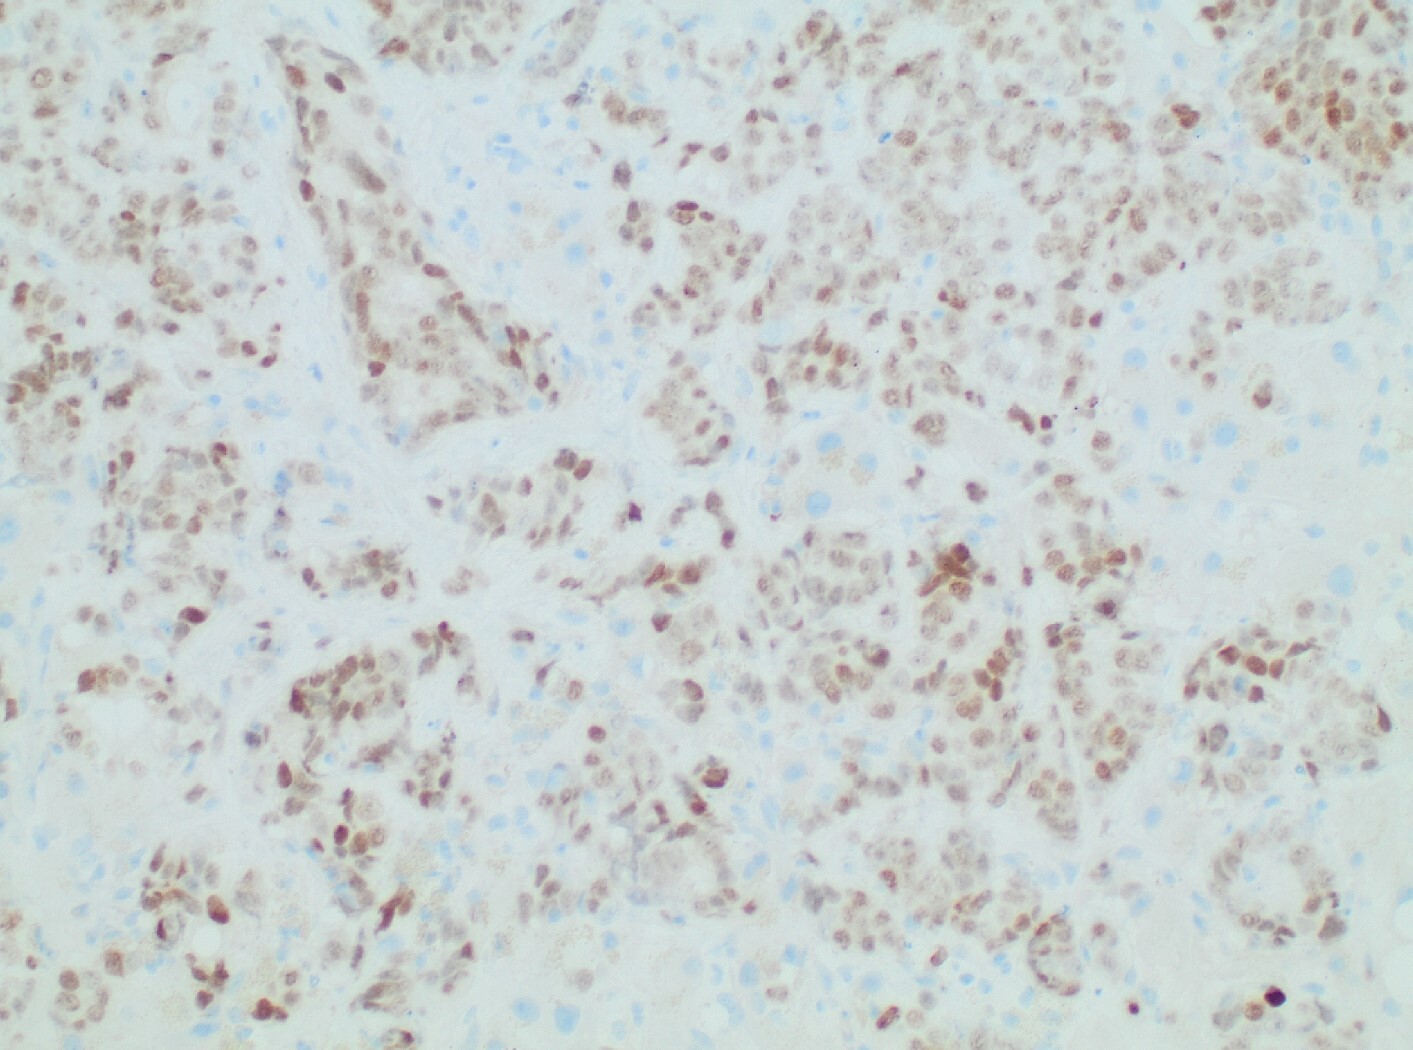

Diagnostic paracentesis was performed and revealed an ascitic protein of 0.9 g/dL, and serum-ascites albumin gradient was calculated to be 2.8. Given his prior history of docetaxel use, the decision was made to proceed with a trans-jugular non-targeted liver biopsy to rule out medication induced hepatic veno-occlusive disease. Hepatic venous pressure gradient was found to be elevated at 32 mmHg. The liver biopsy revealed infiltrative adenocarcinoma from known primary prostate cancer with immunohistochemical staining significant for positive NKX 3-1 and negative CK7 and CK20 (Figures 1-5). The patient was diagnosed with ALF secondary to infiltrative prostate cancer and did not meet transplant criteria due to malignancy. Considering the information provided via the liver biopsy, it was determined the lutetium (177Lu) vipivotide tetraxetan therapy would be ineffective. After extensive conversation, the patient and his family opted for home hospice to spend valuable time with loved ones. The patient was discharged after a total hospital stay of 6 days. He expired less than 2 weeks after discharge.